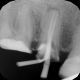

Rentgenowskie zdjęcie będzie także potrzebne czy wręcz niezbędne podczas przygotowań do leczenia kanałowego. Dzięki zdjęciu RTG lekarz będzie w stanie prawidłowo ocenić różne parametry zęba takie jak długość korzenia czy ilość kanałów.

Nasze przykładowe realizacje :